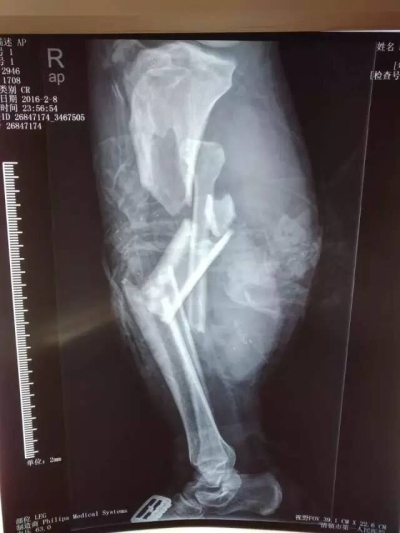

950分,罗xx,男,30岁,双小腿压榨伤。经转清镇市和贵阳两个医院后,于伤后约6小时急诊就诊于我院。入院后,诊断为:1.创伤失血性休克,2.右腘动静脉、胫神经、腓总神经损伤,3.右胫后动脉损伤,4.右胫腓骨开放性粉碎性骨折,5.右腓骨头骨折脱位,6.右小腿广泛皮肤软组织潜行剥脱伤,7.右大腿皮肤软组织挫伤,8.左胫腓骨粉碎性骨折。由于伤者伤情严重,又是在伤后6小时才辗转来到我院,延误了救治时间,失血3500ml,患者面临截肢的危险,伤情已经危及生命。时间紧迫刻不容缓,作为显微外科技术名列全省领先地位的贵阳市显微外科中心,我院立即开通绿色通道,骨三科值班医护人员在学科带头人宋开芳主任的指示下,积极补液输血,纠正患者休克,维持生命体征平稳,作好术前一切准备工作;检验科以最快速度为患者作了术前化验检查,输血科为患者作了交叉配血并准备了充分的血液供应;麻醉师唐恒、龙莎快速稳妥地为患者进行了麻醉。杨颇副主任和姜昱林医师从初二上午10时上手术台,历时12小时的手术,术中输血3000ml,重建了肢体血液循环,挽救了患者的肢体。目前,患者生命体征平稳,肢体血液循环稳定。经骨三科、麻醉手术科、输血科、检验科、总务科等相关科室有效积极的配合,成功对患者进行了救治。